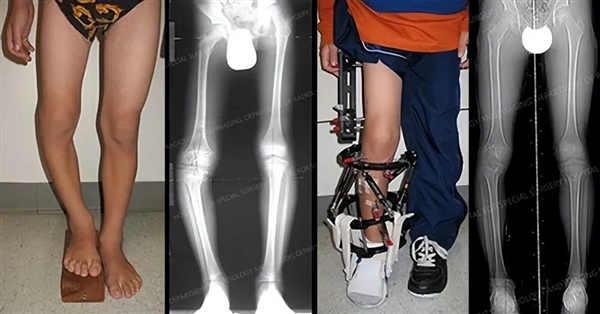

腿部畸形矫正案例

简单来说,就是先敲断骨头,然后体外安装一种牵引设备,反方向两边拉伸,来刺激骨头再次生长,最终通过骨头的延长来增加身高,所以也叫肢体延长术。

切除一截股骨后,再植入金属设备将两截断骨接上固定住,等切开处骨头愈合再将金属取出,腿外部不需要用其他设备固定。